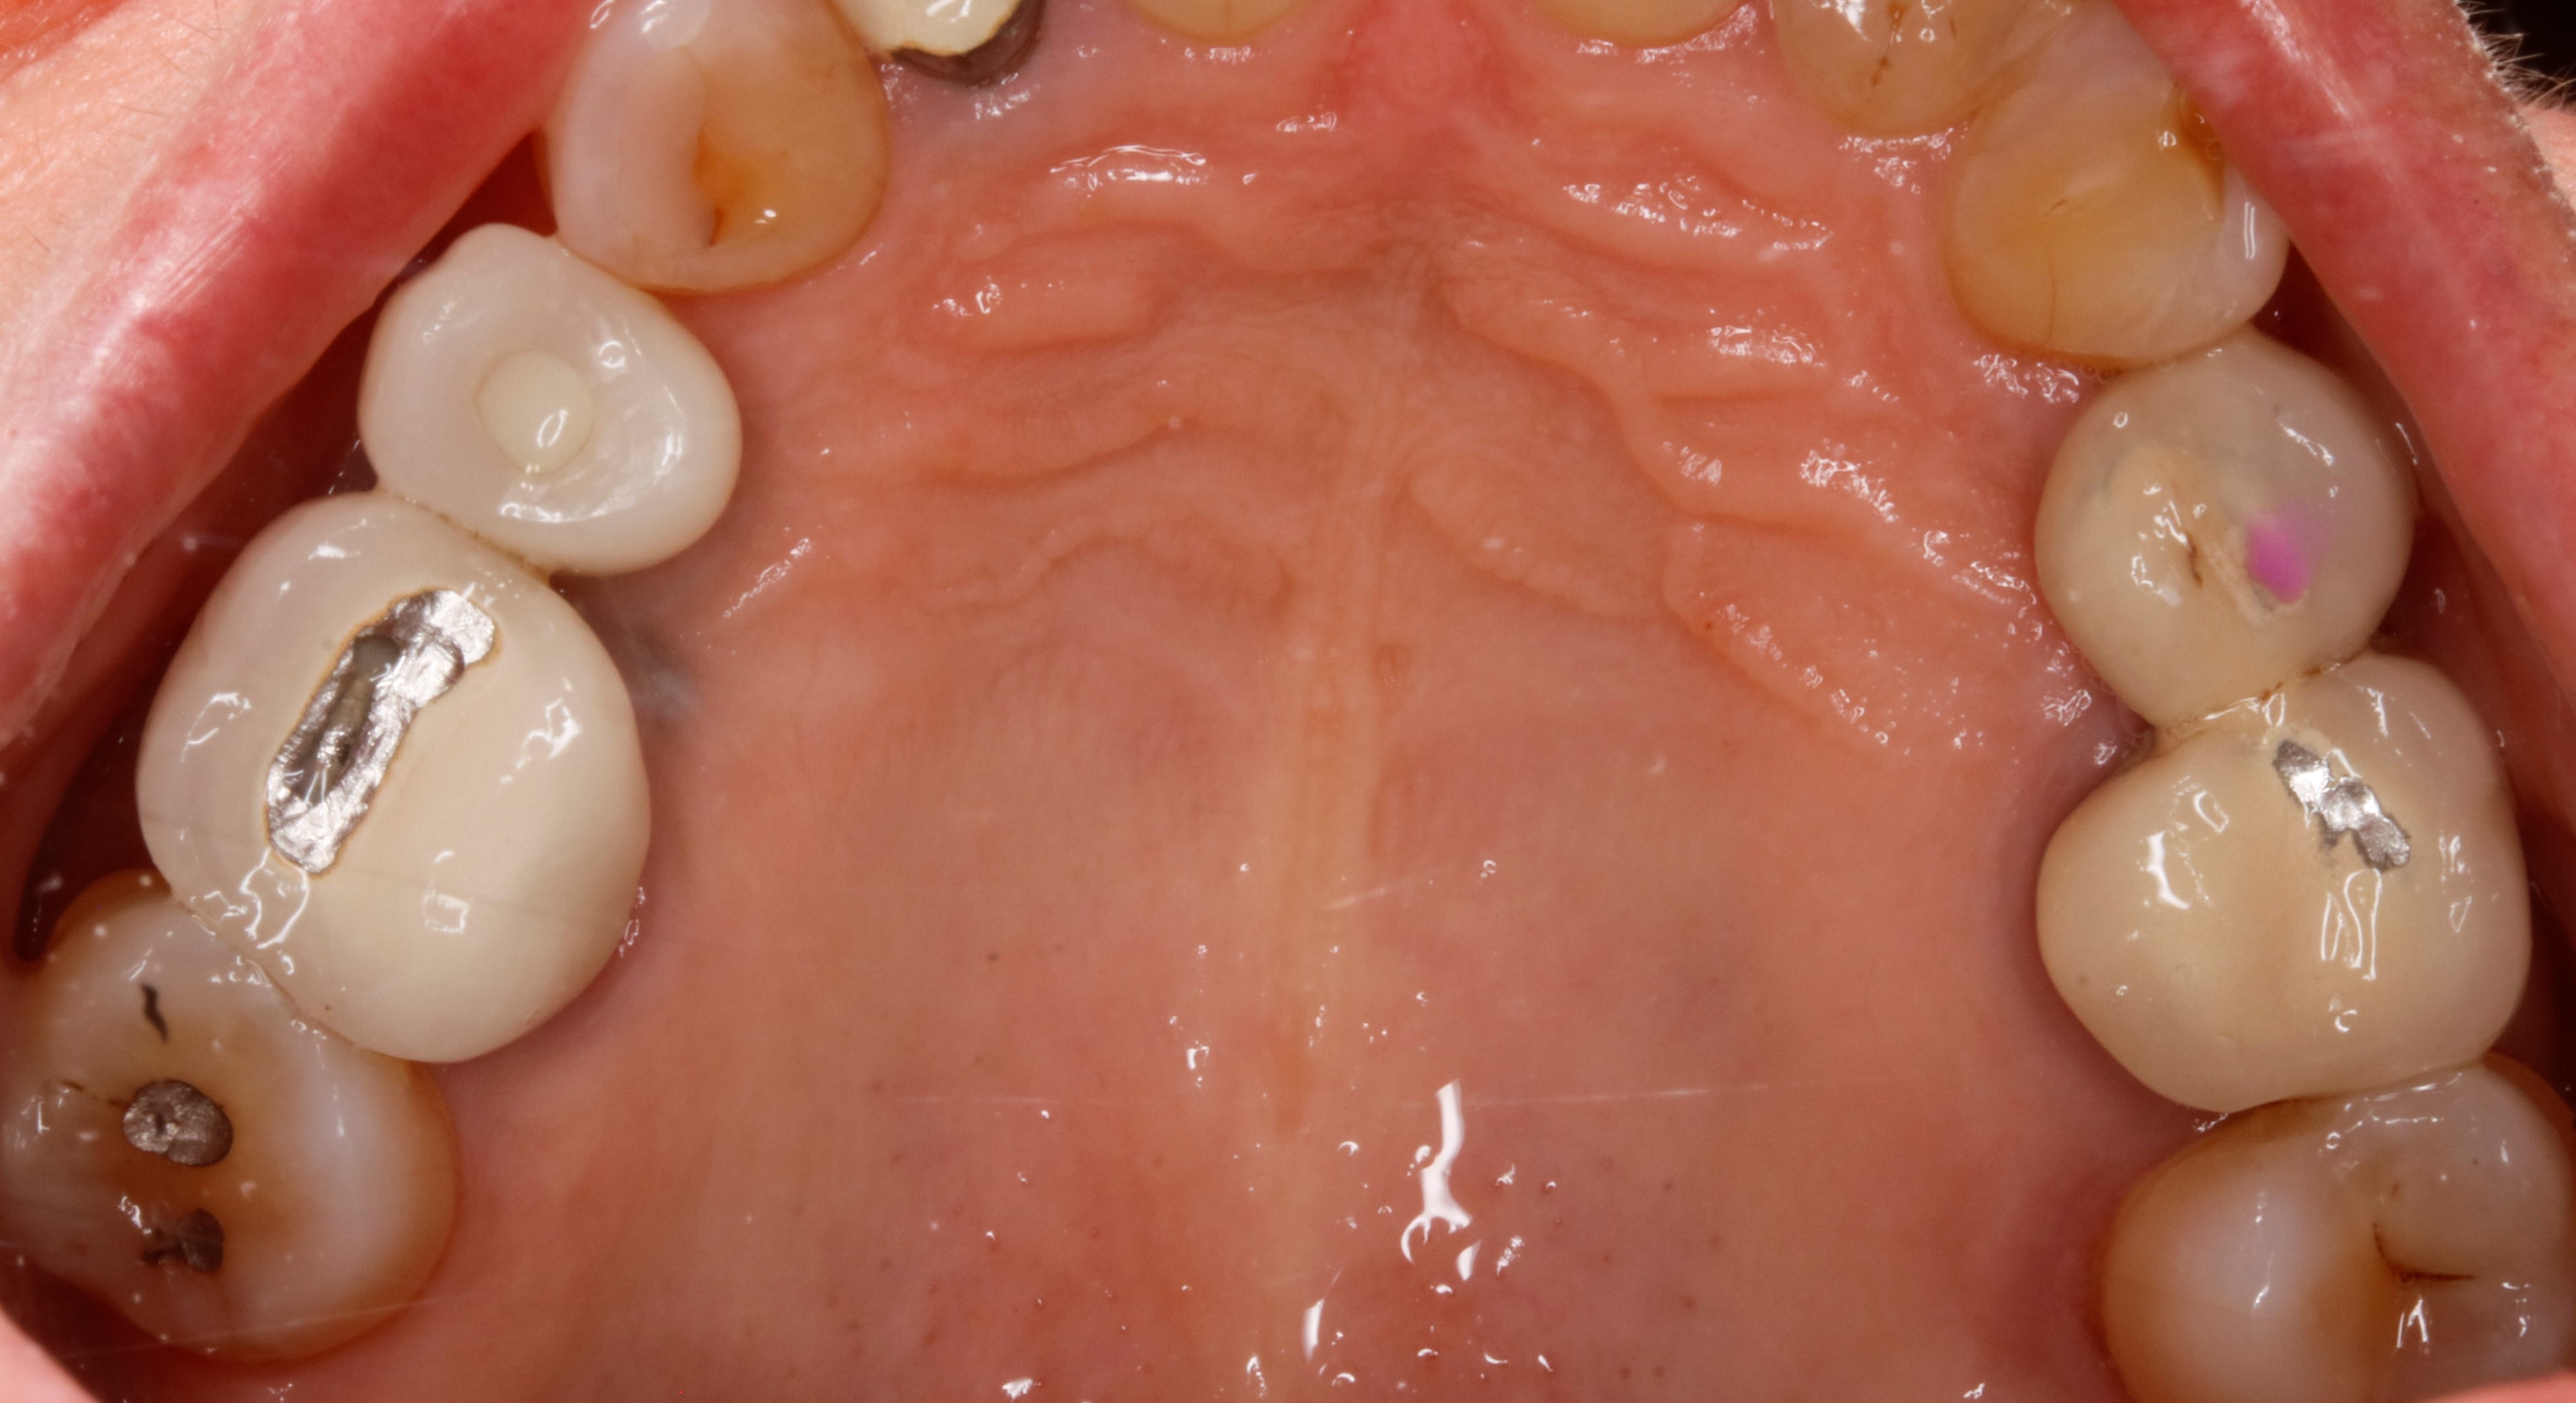

Le calage post est merdique en particulier secteurs 2 et 3 donc 26/27 et 36/37

Ça forme une marche quelle veut virer donc mode meule avant arrière sur ce côté et dans le mouvement la 12 dégage

Bilan, tu refais comme il faut ces 4 couronnes pour remettre comme il faut les courbes et le problème est grandement géré

j y vois une supraclusion , de l usure , un passif orthodontique par l absence de PM , une asymétrie des incisives du bas , un sur guidage ant , bref que cette occlusion d aujourd'hui , n est certainement pas celle d'hier et qu il y a bien eu une dérive latérale .

la ceram de molaire ( tres récente ) est déjà percée , la 22 est déjà sur le métal , on va donc partir sur un diagnostic de surélévation pour remettre à l initial .